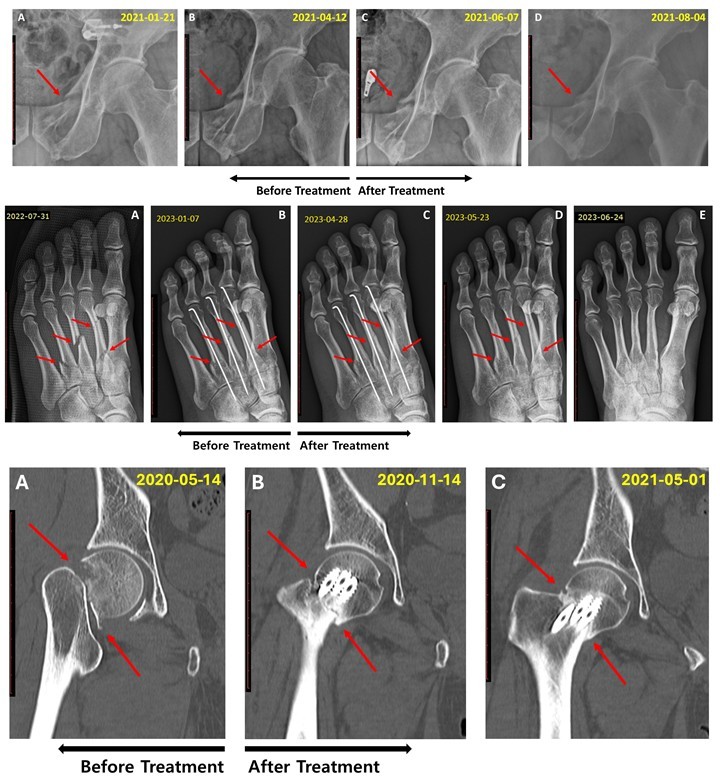

접골탕, 기존 치료 무반응인 지연유압 골절에 효과 확인

5개월 이상 장기 지연유합도 접골탕 치료 가능성 확인

수술 어려운 환자들에 대안 제시

[한의신문] 한국한의학연구원(원장 이진용·이하 한의학연)은 골절 치료 한약인 접골탕이 5~6개월 이상 지속된 골절 지연유합 환자들의 치료에 효과적이라는 연구 결과를 지난 24일 발표했다.

한의치료 사례의 과학적 검증을 지원하는 코어(KORE) 프로젝트의 일환으로 진행된 이번 연구는 국제 학술지인 ‘Frontiers in Endocrinology’(IF 4.6)에 지난달 30일 게재됐다.

한의학연 관계자는 연구결과 접골탕은 골반뼈, 다발성 중족골, 대퇴골 경부 골절 지연유합에서 효과를 보였다이번 연구는 기존에 알려진 접골탕의 골밀도 개선 효과와 3개월 이내 지연유합 치료 효과에서 더 나아가, 5~6개월 이상 지속된 난치성 지연유합에서도 효과가 있다고 설명했다.

한의학연에 따르면 연구에 보고된 접골탕은 당귀, 천궁, 속단 등 여러 한약재를 비압력 탕전방식으로 2시간 열수 추출한 한약이다.

또 접골탕의 주요 성분인 노다케닌(nodakenin)’은 골모세포 분화를 촉진하고 골흡수 세포 형성을 억제하는 이중 기전을 통해 골재생에 기여하며, ‘페룰산(ferulic acid)’은 혈관 내피 기능을 향상시켜 골절 부위의 혈액 공급을 개선하는 것으로 알려져 있다고 한의학연 관계자는 밝혔다.

연구책임자 양창섭 박사는 이번 연구는 기존 치료법으로 충분한 회복을 이루지 못한 장기 지연유합 환자들에게 접골탕이 효과적인 보완 치료 옵션이 될 수 있음을 보여준다특히 수술적 개입이 어려운 환자나 재수술을 고려해야 하는 상황에서 대안이 될 수 있다고 설명했다.